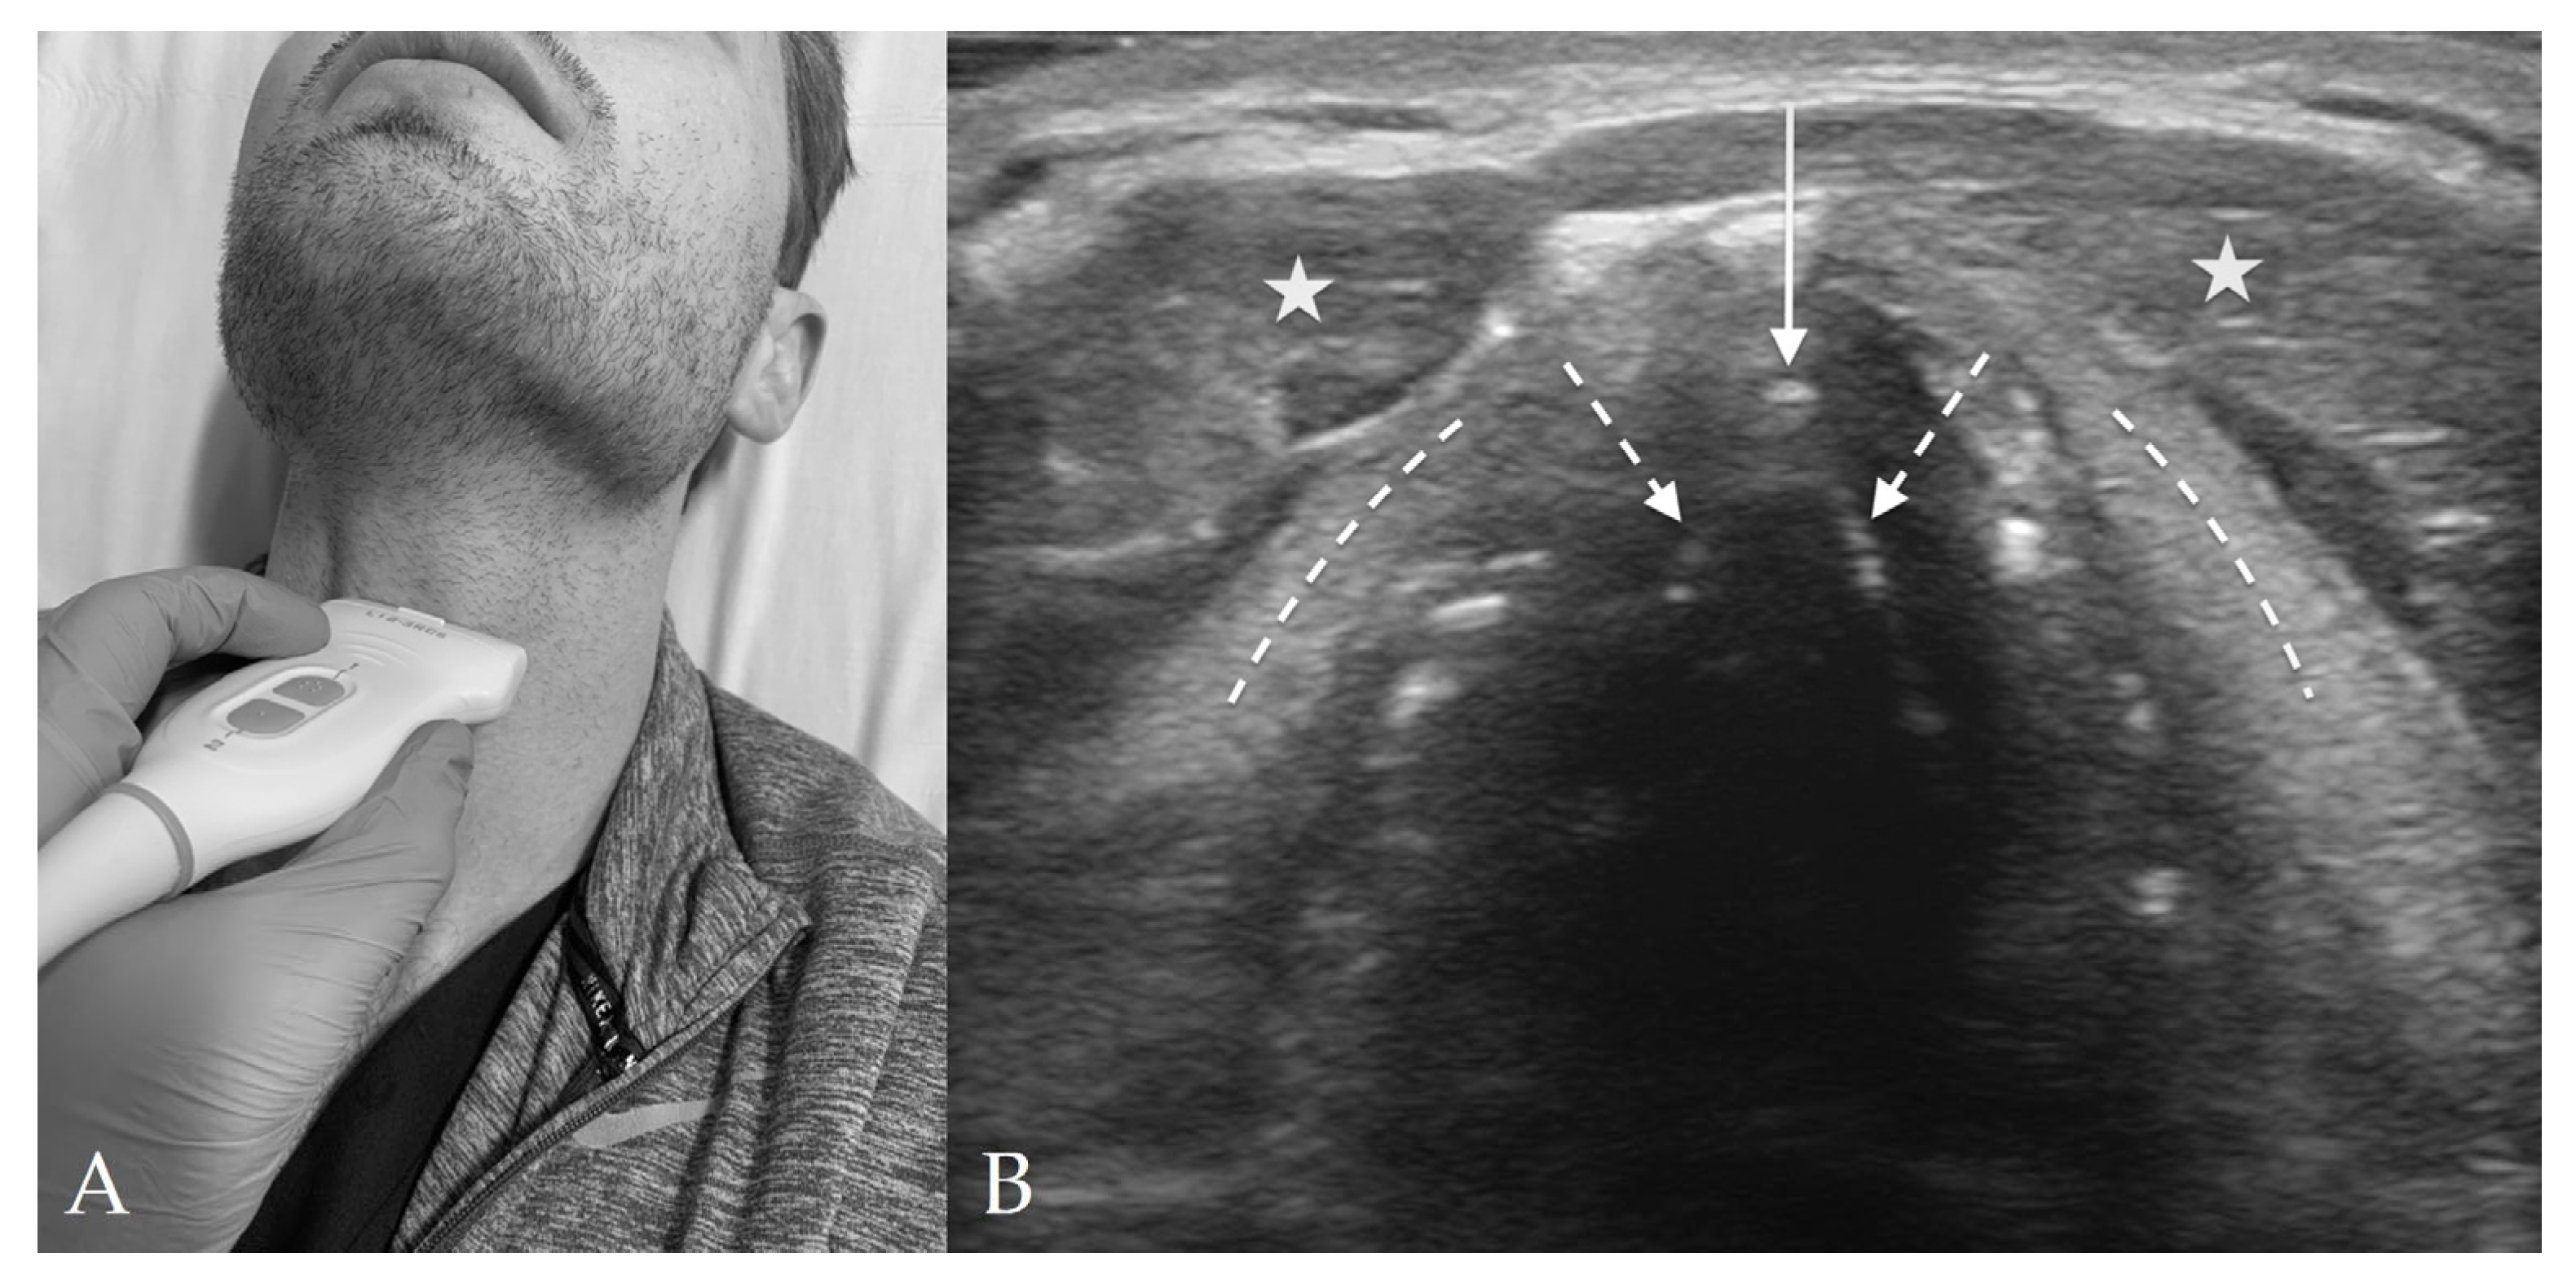

4.4. Cricothyroid View

4.5. Suprasternal View

8. Preparation for Cricothyrotomy